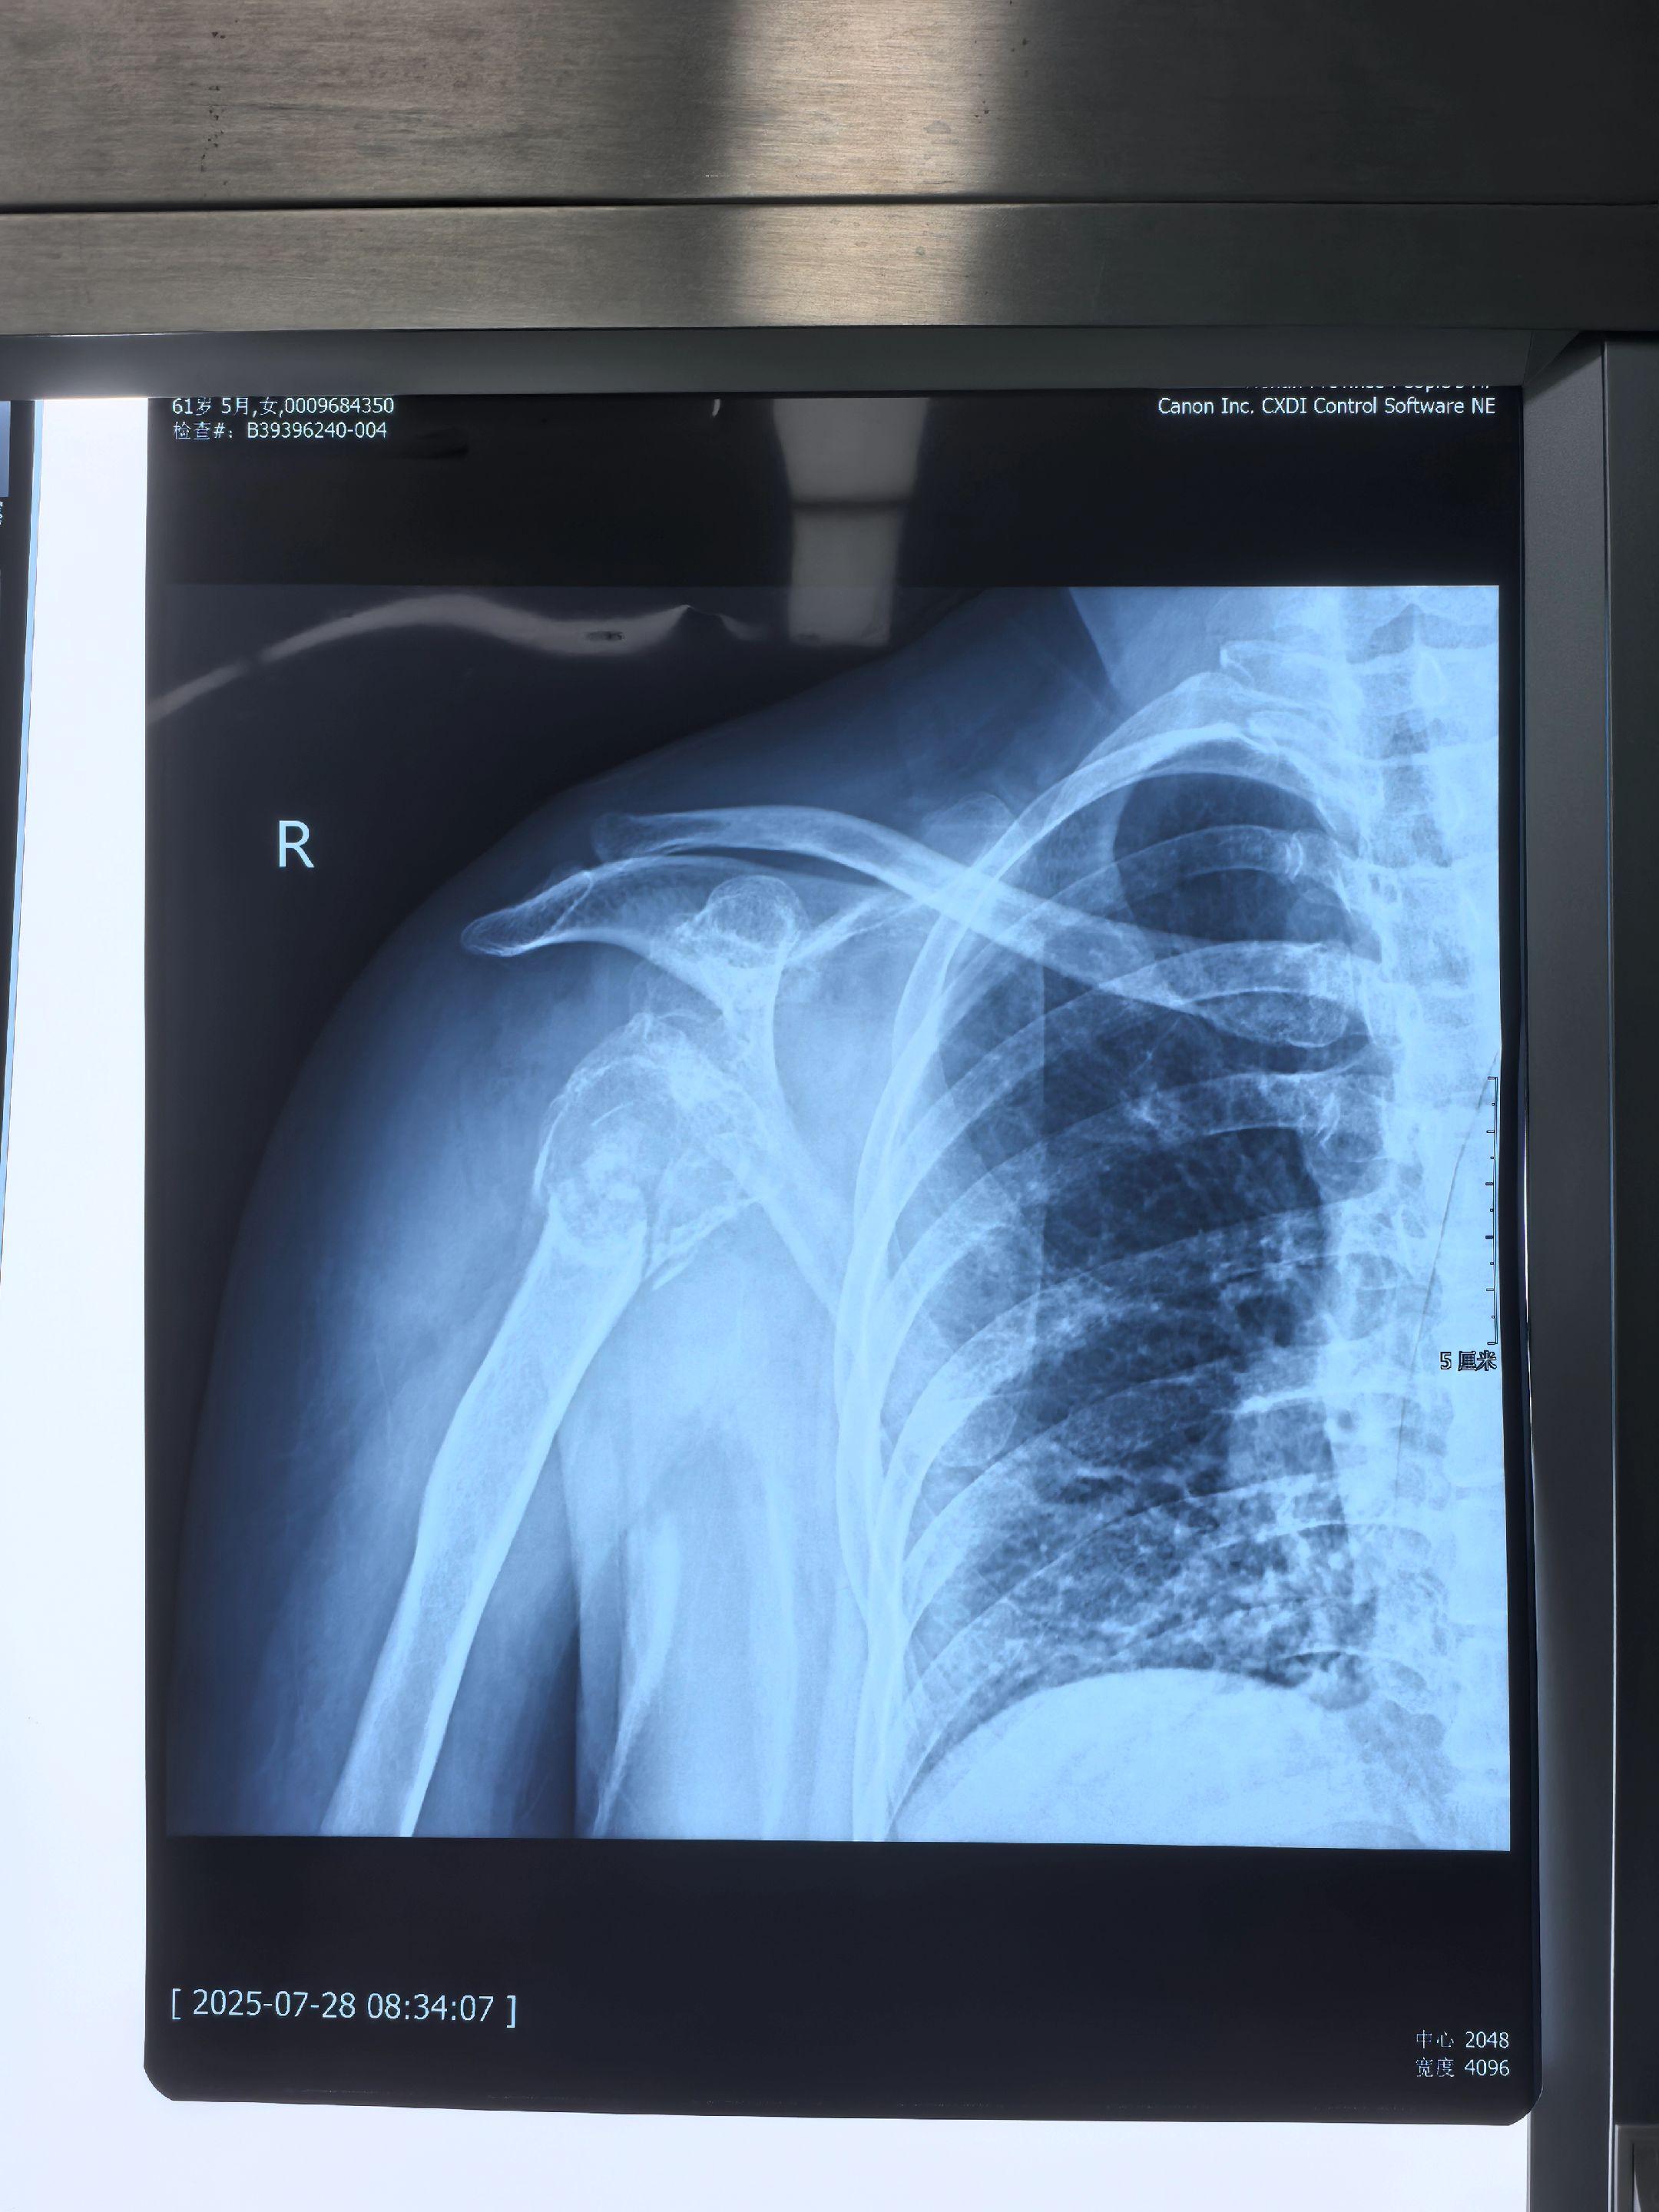

反肩置换。反置式全肩关节置换术(RTSA),拯救不可修复性肩关节病损的终极武器。本例肱骨近端粉碎性骨折,合并骨性关节炎,肩关节盂发育畸形,RTSA新伤旧疾一并解决。